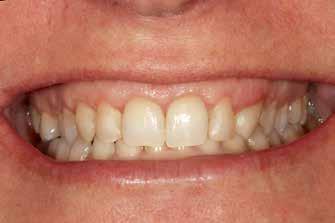

Before After

Deep amalgam staining presents one of the most difficult restoration situations to clinicians. In this case only the Transcend composite Universal Body shade was used to replace the amalgam no blocker needed. Note the excellent color blending of the preserved oblique ridge.